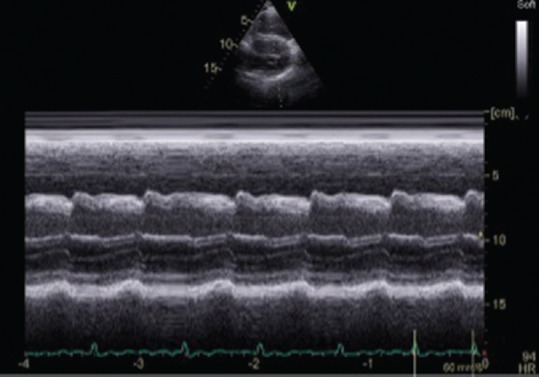

Abstract Image